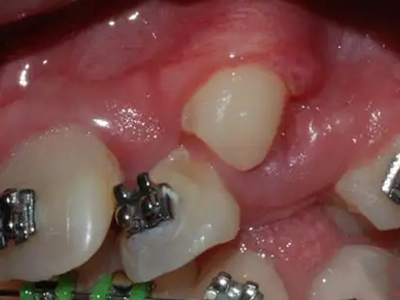

阻生牙是指由于邻牙、骨或软组织的阻碍而只能部分萌出或完全不能萌出,且以后也不能萌出的牙。引起牙阻生的成因,主要是由于颌骨缺乏足够的空间容纳全部恒牙。常见的阻生牙为下颌第三磨牙、上颌第三磨牙及上颌尖牙。

阻生牙可反复引起冠周炎,或引起邻牙牙根吸收和破坏,位置不正,不能完全萌出,好发部位是上、下颌第三磨牙。

发育正常的牙齿同时正畸治疗又不需要进行拔牙矫治,通常需要对阻生牙进行牵引治疗,引导进入牙弓,而对于发育异常的阻生牙加之正畸治疗需要进行拔牙矫治,通常可以考虑将阻生牙拔除,而避免再拔发育正常的前磨牙,即降低了正畸治疗的难度及不确定性,又保留了相对正常的牙齿。